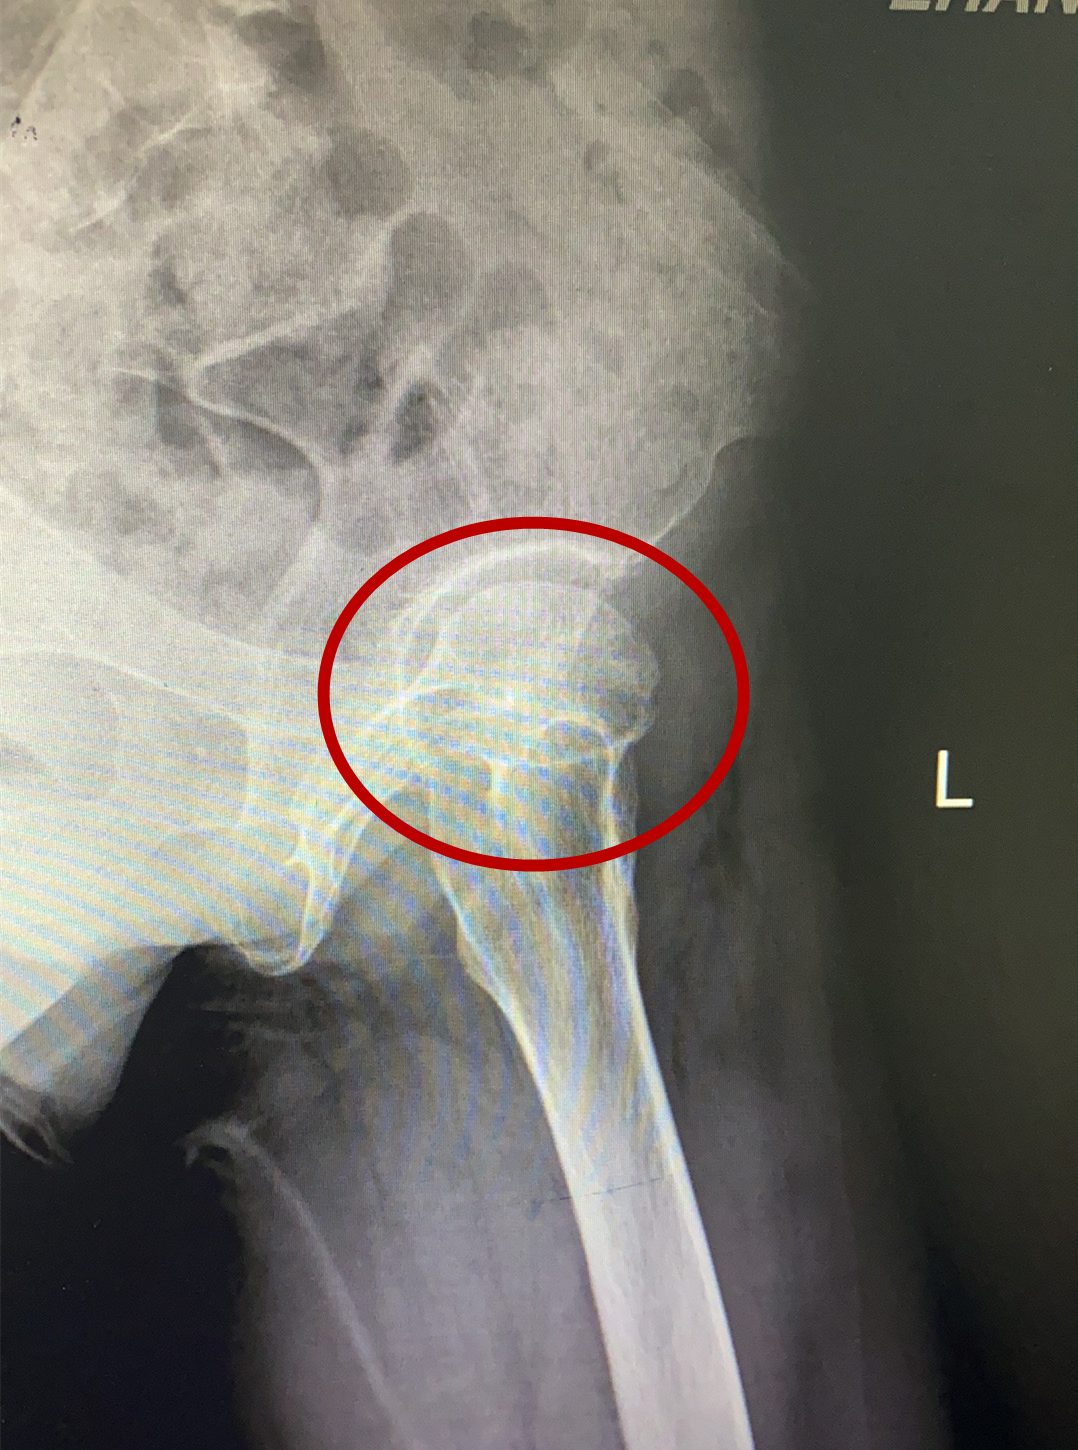

术前影像

骨关节专家林石明副院长及其医疗小组成员,经过反复研究患者的核磁共振及CT三维血管重建等资料后,考虑为左侧股骨头坏死,程度在二期到三期之间,具有“带血管蒂腓骨骨移植”手术指征。目前国际上公认“带血管蒂骨移植”这项保髋技术成功率较高,但该手术技术难度较大,需要把小腿上约8cm腓骨连同临近的腓骨动脉血管截一段下来,植入股骨头颈的坏死区域,在显微镜下,将腓骨动脉与股骨头临近血管进行对接缝合,重建血供让坏死股骨头获得新生。该手术一旦成功,将为林女士保留住髋关节功能,能较快恢复日常劳动,且费用较低。